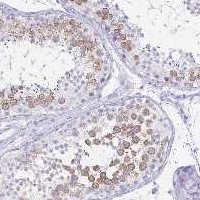

Immunohistochemical staining of human testis shows strong cytoplasmic positivity in cells in seminiferous ducts.